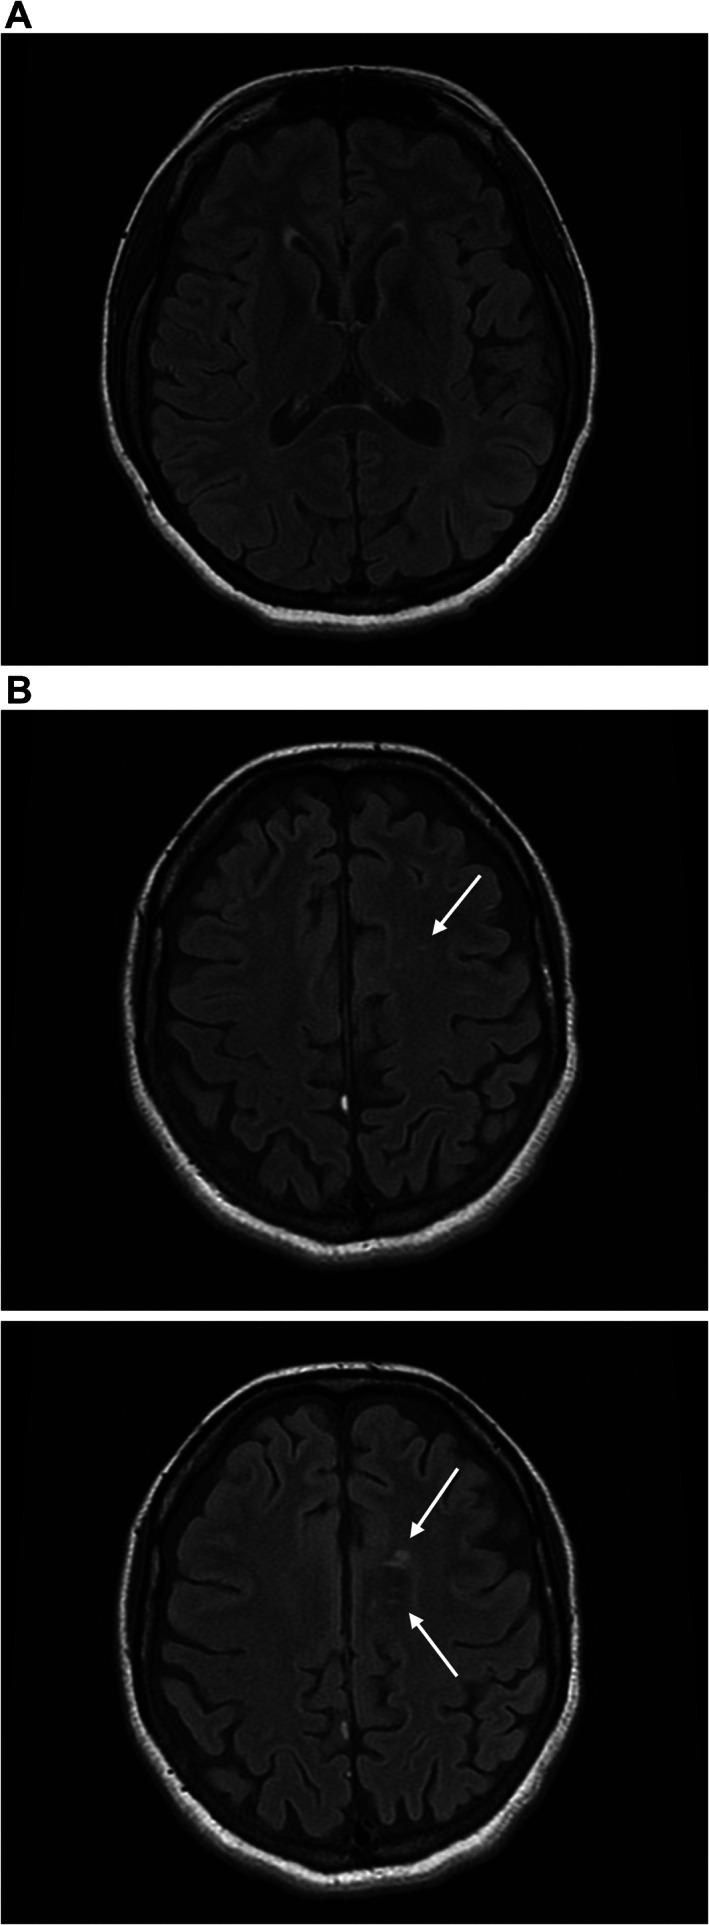

A Hispanic woman with unremarkable medical history experienced progressive lower-limb spasticity in her 20s and received a diagnosis of HSP. She developed significant gait abnormalities and is unable to walk without assistance. More recently, two Hispanic brothers with childhood-onset manifestations including lower-limb spasticity, developmental delays, and seizures presented with suspected HSP. All three patients were ultimately diagnosed with ARG1-D based on plasma arginine several-fold above normal levels and loss-of-function variants. Disease progression occurred before ARG1-D was correctly diagnosed.

一名无明显病史的西班牙裔女性在20多岁时出现进行性下肢痉挛,并被诊断为HSP。她出现了明显的步态异常,没有帮助无法行走。最近,两名患有儿童期发病症状(包括下肢痉挛、发育迟缓及癫痫发作)的西班牙裔兄弟疑似患有HSP。基于血浆精氨酸水平高于正常水平数倍及功能缺失变异,所有三名患者最终被诊断为ARG1-D。在ARG1-D被正确诊断之前疾病已经进展。